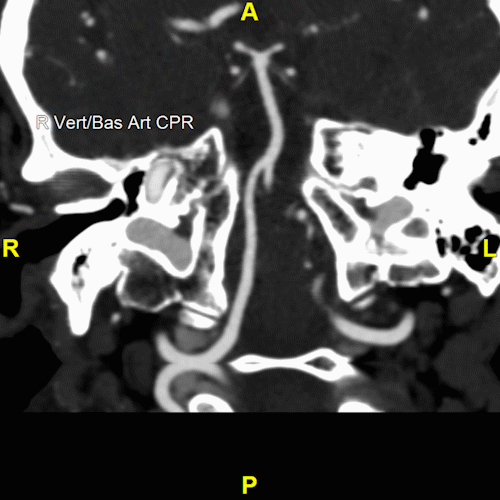

3D imaging for head and neck angiograms is a diagnostic tool that significantly enhances the detection and assessment of vascular conditions such as cerebral aneurysms, and stenosis, with a particular focus on the Circle of Willis. This imaging process allows providers to see the presence of calcium within aneurysms, the specific configuration of aneurysm necks, and the origins of vital vessels. Understanding these details is crucial for determining the most appropriate treatment pathway for patients.

These renderings also reveal stenosis or dissections in carotid or vertebral arteries, providing a view that may aid in diagnosis and treatment planning. These images are available within 45 minutes after CT acquisition, ensures timely decision-making.

This service creates many series of images. This includes axial, coronal, and sagittal maximum intensity projections (MIPs), as well as curved planar reconstructions (CPRs) of the left and right carotid arteries. Additionally, volumetric rendering (VR) of the Circle of Willis offers insights into the vascular architecture, aiding in the comprehensive evaluation of these structures.